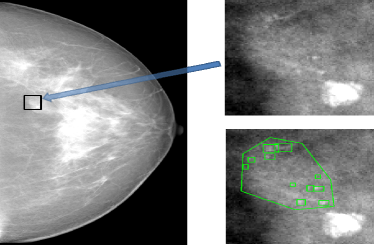

One application of such a knowledge transfer problem is the detection of microcalcification (MC) groups in 3D digital breast tomosynthesis (DBT). A MC group is composed of multiple small and similar individual MCs, and is considered a possible sign of breast cancer. Because MCs may be small and lack enough contrast (as in Figure 1(a)), they can be easily missed by radiologists during the routine screening process. Needless to say, a MC group computer-aided detection (CAD) can help radiologists locate suspicious regions and help them make diagnostic decisions.

Figure 1: (a) Left: An example of a malignant mammography screening image from GE Senographe mammography system showing the difficulty of finding MC groups. Right top: The local MC group region. The region is small and MCs are barely visible even with adjusted window level to enhance contrast. Right bottom: The ground truth of individual MCs (the bounding boxes), and the malignant group (the convex hull contour). (b) An example of GE SenoClaire DBT volume with manually labeled group contour on one slice (the green contour). The inter-slice boundaries of the group are labeled as green points.

A large number of literature has been reported on creating CAD system for MC groups in 2D mammography (as in Figure 1(a)). However, publications on CAD for recently emerged DBT (as in Figure 1(b)) are very limited. This is due to the difficulty of collecting enough cancer cases to train a DBT CAD from scratch. Instead, most researchers built systems on small DBT datasets with limited training [1, 2] or applied a mammography CAD directly on slices or projections of DBT volumes [3, 4, 5].